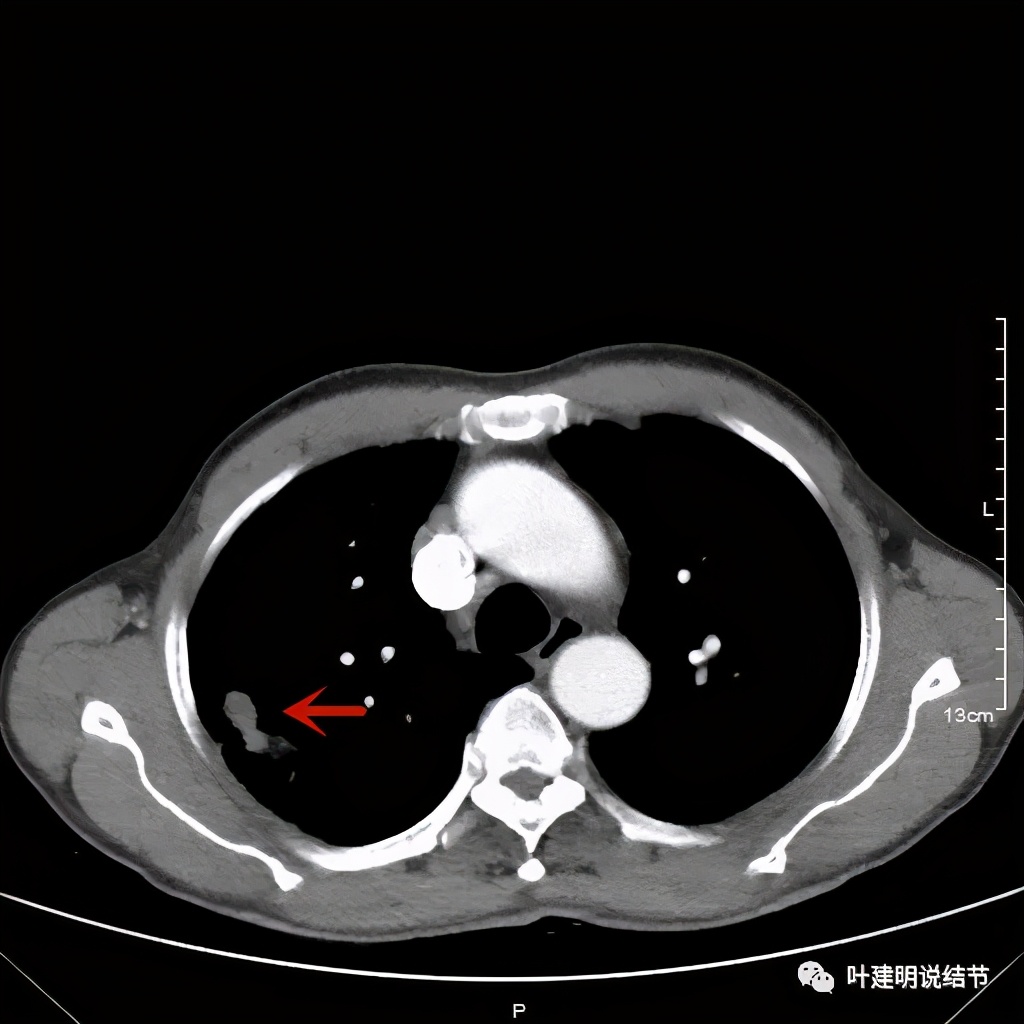

金华的某A,今年66岁,前几天在当地医院查胸部CT平扫发现右上肺占位,当时来找我看时,我想首先肺内占位是要警惕肺癌的,建议其住院进一步做增强CT,以及完善其他相关检查。其中增强CT报告示:右上叶约7*6厘米的肿块,增强后显著强化。而且某A曾于2018年5月在本院做过肺部CT,当时右上肺没有病灶的。我们先来看这次的CT图像:

红色示病灶,绿色示病灶旁边有磨玻璃成分,但较为模糊;蓝色箭头示病灶与胸膜间有牵拉,但力度不太够。

以上诸图是纵隔窗

总体上感觉,病灶比较大,不规则,不是圆形或圆形生长,周围有模糊磨玻璃影(考虑炎性渗出性?),虽有胸膜牵拉,但力度不够;增强有显著强化。病灶明显却无明显临床症状,普通感染是不像的,要么是结核,要么是肺癌。但肺癌的话,在2年前没有,2年内长到这么大,恶性程度应该很高,但其纵隔淋巴结却没有明显肿大。而且病灶的边缘部分过于光滑,没有见到肿瘤的细毛刺,膨胀性也不够。整体看病灶有点像“腰子”形,弯弯曲曲的。所以我的感觉更倾向结核性。查了肿瘤筛查指标如下: